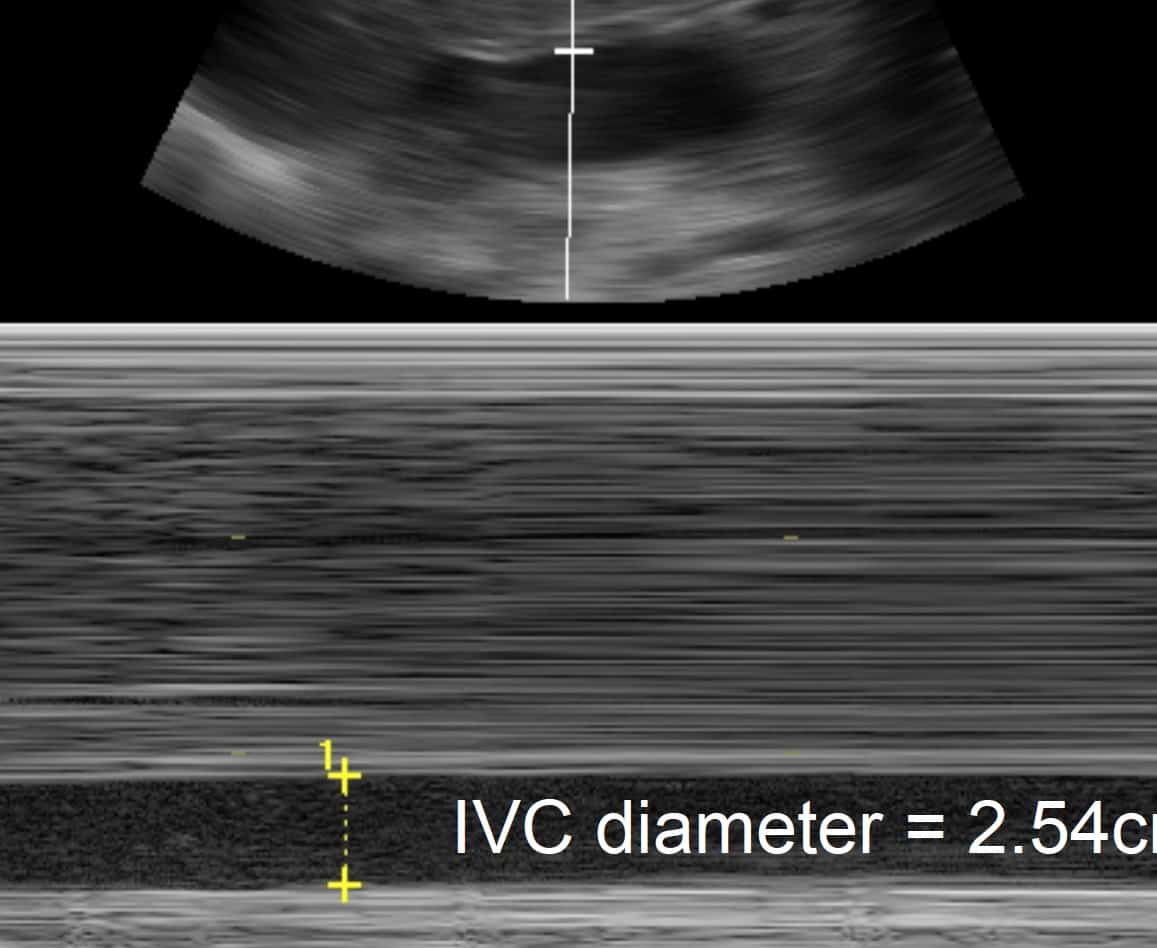

Tamponade M Mode. Note how the inward movement of the. Transthoracic echocardiography for pericardial effusion.

Note how the inward movement of the. Transthoracic echocardiography for pericardial effusion.